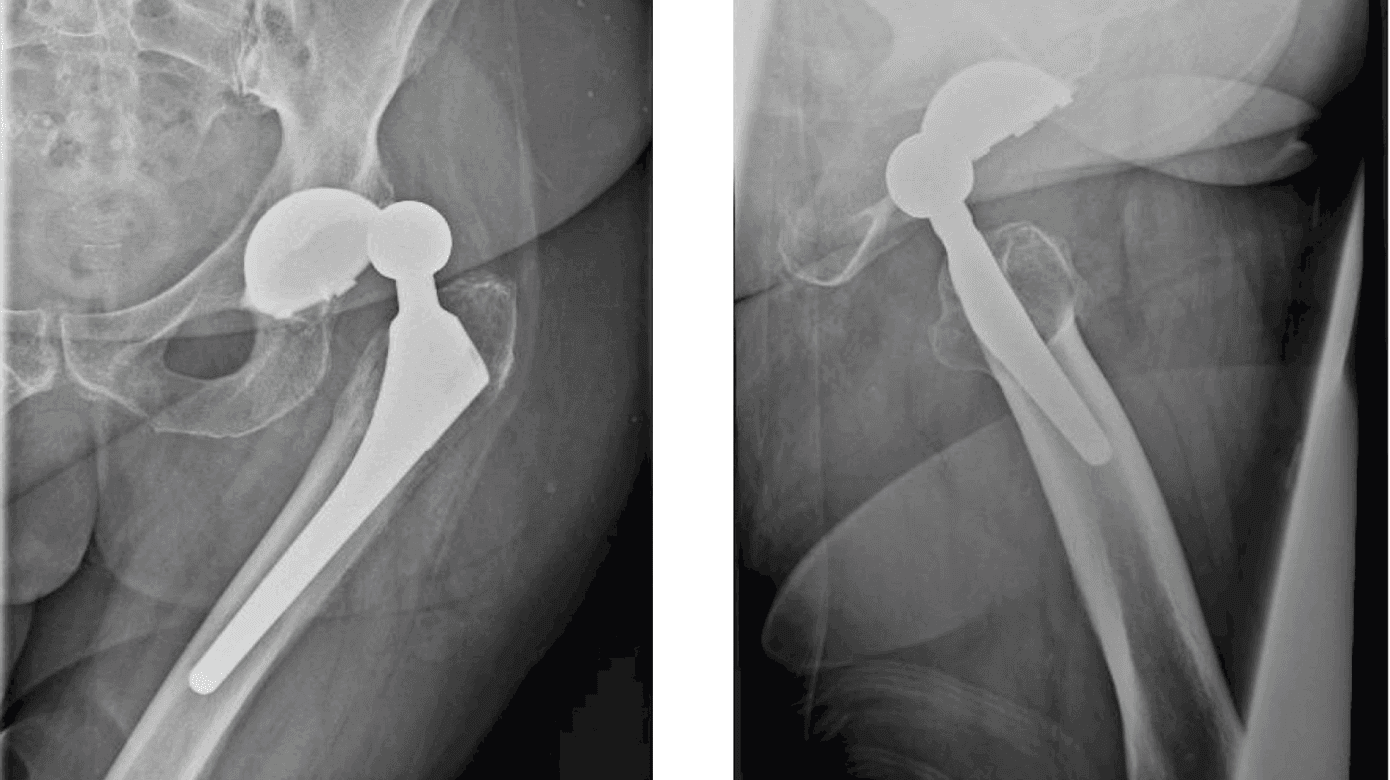

THA-luksation defineres som komplet displacering af metalhovedet, dvs. caput, fra acetabularkomponenten, dvs. cuppen. Den typiske luksation opstår i forbindelse med hurtige bevægelser med en for kraftig fleksion i hoften, evt. kombineret med indadrotation. Det resulterer i en posterior luksation (Figur 1), hvorimod strækning af hoften og samtidig udadrotation kan føre til anterior luksation. Klassiske mekanismer herfor omfatter mobilisering fra en lav stol eller seng, fremadbøjning for at tage strømper på eller binde sko eller ved et faldtraume [10]. Luksationen medfører øjeblikkelig intens smerte og manglende evne til mobilisering. Klinisk set er man sjældent i tvivl om diagnosen, og der er fejlstilling og forkortning af benet (flekteret, indadroteret hofte ved posterior luksation; ekstenderet, udadroteret hofte ved anterior luksation). Røntgenundersøgelse er nødvendig for at bekræfte diagnosen og for at udelukke periprostetisk fraktur. Langt størstedelen af luksationerne kan behandles med lukket reponering under enten sedation eller en kort general anæstesi. Akut åben kirurgi er sjældent nødvendig [11].